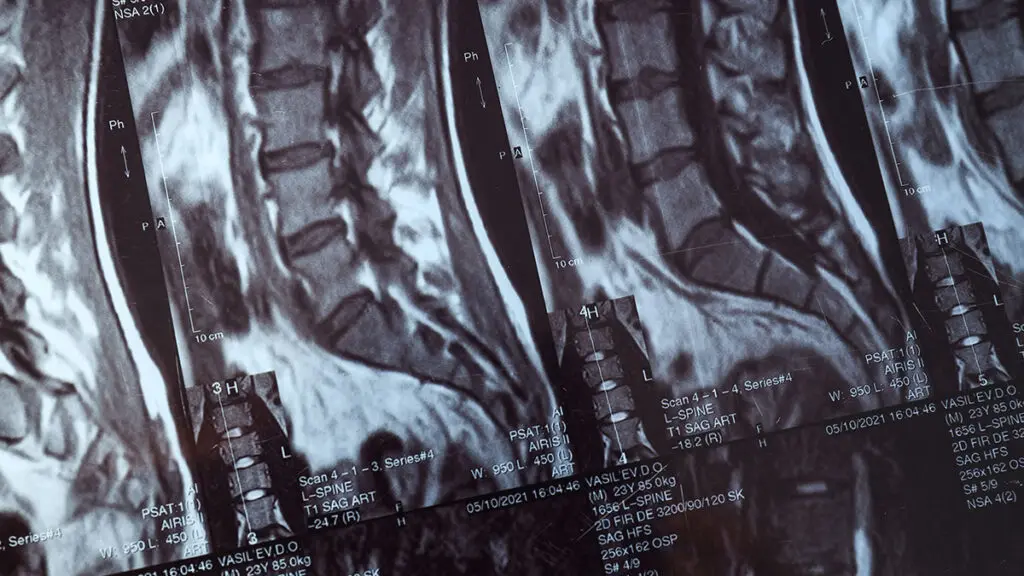

Una visita colonna vertebrale presso Global Spine Solutions è il primo passo per ricevere una diagnosi accurata e un piano terapeutico personalizzato per la tua patologia vertebrale. Durante la visita, il neurochirurgo analizza la sintomatologia, esamina gli eventuali esami diagnostici disponibili (RMN, TAC, radiografie) e valuta le opzioni di trattamento più appropriate.